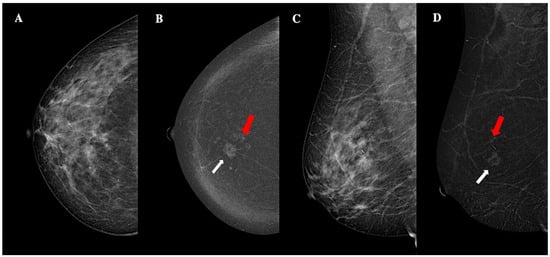

Figure 6.

Contrast-enhanced mammography in a 54-year-old patient with BI-RADS 5 lesion. CEM low-energy images (panels A,C) show pseudonodular opacities with associated microcalcifications and ill-defined margins are observed in the lower inner quadrant. These findings are more distinctly visualized in the recombined CEM images (panels B,D). The white arrows highlight the main lesion, approximately 14 mm in size, exhibiting moderate conspicuity, heterogeneous enhancement, and ill-defined margins. Additionally, two similar foci, measuring approximately 8 mm and 4 mm, with comparable morphological features, were identified (red arrows). The lesion was diagnosed as a unilateral, multifocal, grade 3, invasive, Her2-enriched ductal cancer, without lymphovascular invasion.